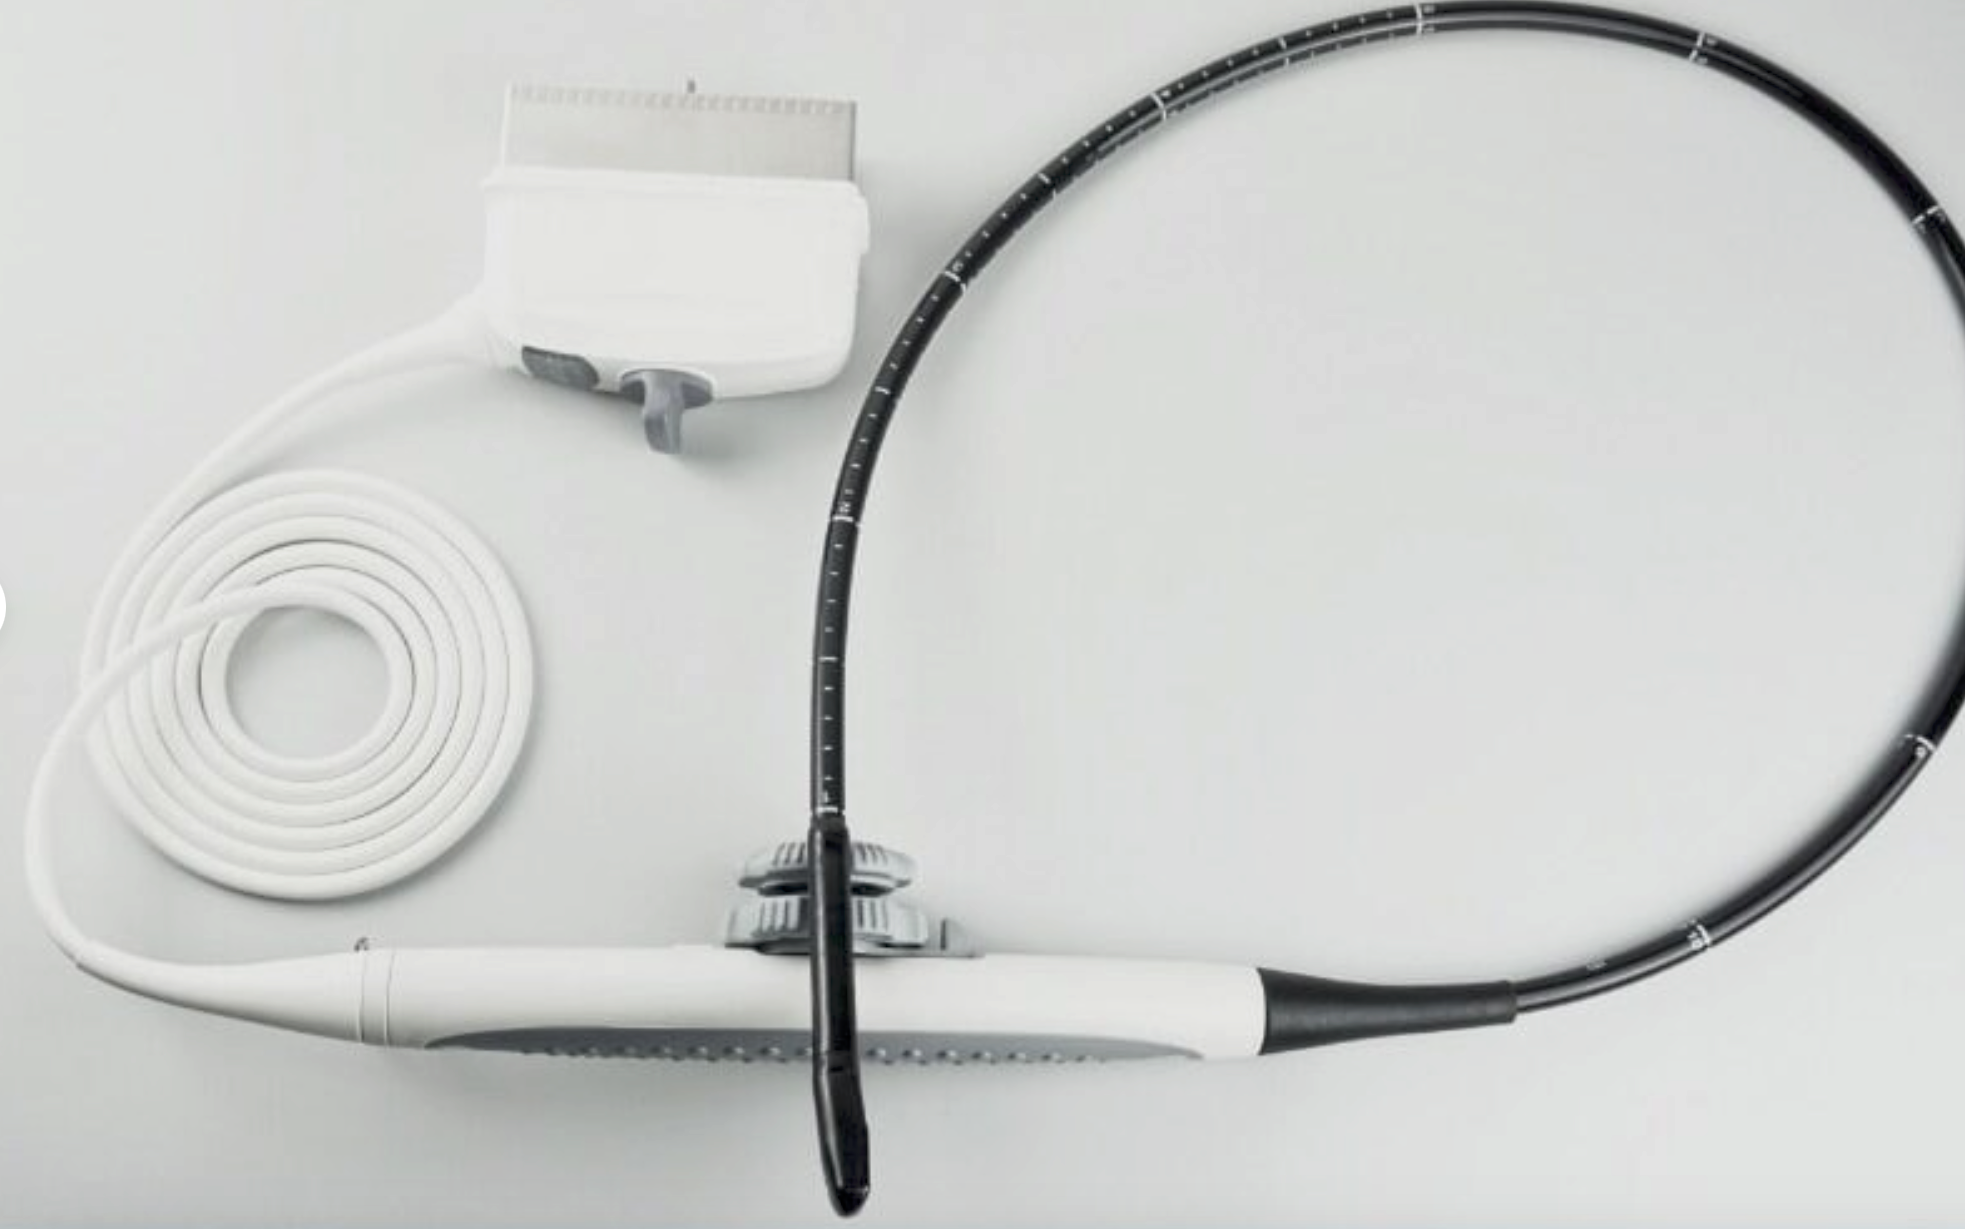

Seller Notes:âFully functional. Tested using a GE Logiq 9 with a breast phantom. Shows signs of use. Includes everything shown.â

Model: GE 4D8C 3D/4D Curved Array 3.5-9MHz Ultrasound Tra

The GE 4D8C ultrasound transducer probe operates within a frequency range of 3.5-9MHz, making it ideal for high-resolution imaging. This device harnesses advanced 4D capabilities, allowing healthcare professionals to visualize complex anatomical structures in real-time. Consequently, it enhances diagnostic accuracy and aids in better patient care. Users can expect clear and detailed images, which significantly improve evaluation and treatment processes.

This ultrasound transducer is versatile and adapts to various clinical applications, including obstetrics, cardiology, and vascular imaging. Medical practitioners can utilize the instrument for routine examinations and specialized diagnostics. Another advantage is its curved array design, which provides an extended field of view, allowing for easier and quicker assessment of the patient's condition. Hence, it streamlines workflows in busy clinical environments.

The GE 4D8C ultrasound probe integrates user-friendly features that make it easy to operate, even for novice users. The ergonomic design ensures comfort during long procedures, while the intuitive controls provide a seamless experience for the operator. Additionally, the device is lightweight, promoting ease of handling. Therefore, healthcare providers can maintain focus on patient outcomes, knowing that they have reliable equipment at their disposal.